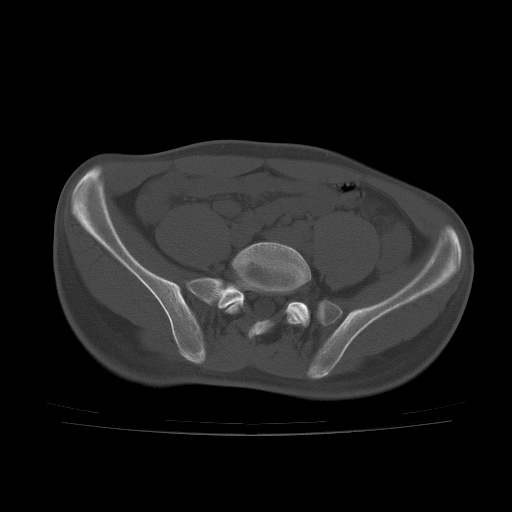

患者男性,18岁 腰腿痛1年  骶髂关节改变本人考虑强直性脊柱炎。

两侧骶髂关节骨质破坏,关节面毛糙,符合强直性脊柱炎骶髂关节改变。

两侧骶髂关节骨质破坏,关节面呈锯齿样改变关节间隙变窄,考虑强真性脊柱炎

两侧骶髂关节骨质破坏以髂骨为主,间隙变窄,强直性脊柱炎